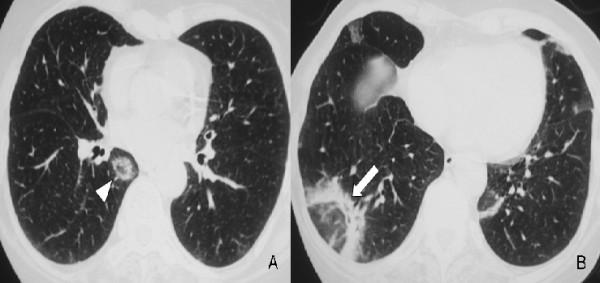

Here, we describe a rare case of acute fibrinous and organising pneumonia, in an otherwise healthy 65-year-old Greek woman who complained of dry cough, fever, weight loss and progressive dyspnoea. She had never been a smoker. Her clinical symptoms showed a rapid deterioration in the two weeks before admission, despite a course of oral antibiotics. After excluding infection and malignancy with routine laboratory tests and flexible bronchoscopy, high resolution computed tomography and video assisted thoracoscopic lung biopsy were performed. Diagnosis was based on radiological features typical of community organising pneumonia coupled with pathologic features characteristic of acute fibrinous and organising pneumonia. The patient was treated with corticosteroids and showed excellent clinical and radiological response three months after treatment initiation.

在此,我们描述一例罕见的急性纤维蛋白性和机化性肺炎病例,患者为一名65岁健康的希腊女性,主诉干咳、发热、体重减轻和进行性呼吸困难。她从不吸烟。尽管接受了口服抗生素治疗,但在入院前两周她的临床症状迅速恶化。通过常规实验室检查和可弯曲支气管镜检查排除感染和恶性肿瘤后,进行了高分辨率计算机断层扫描和电视辅助胸腔镜肺活检。诊断基于社区获得性机化性肺炎的典型放射学特征以及急性纤维蛋白性和机化性肺炎的特征性病理特征。患者接受了皮质类固醇治疗,治疗开始三个月后临床和放射学反应良好。